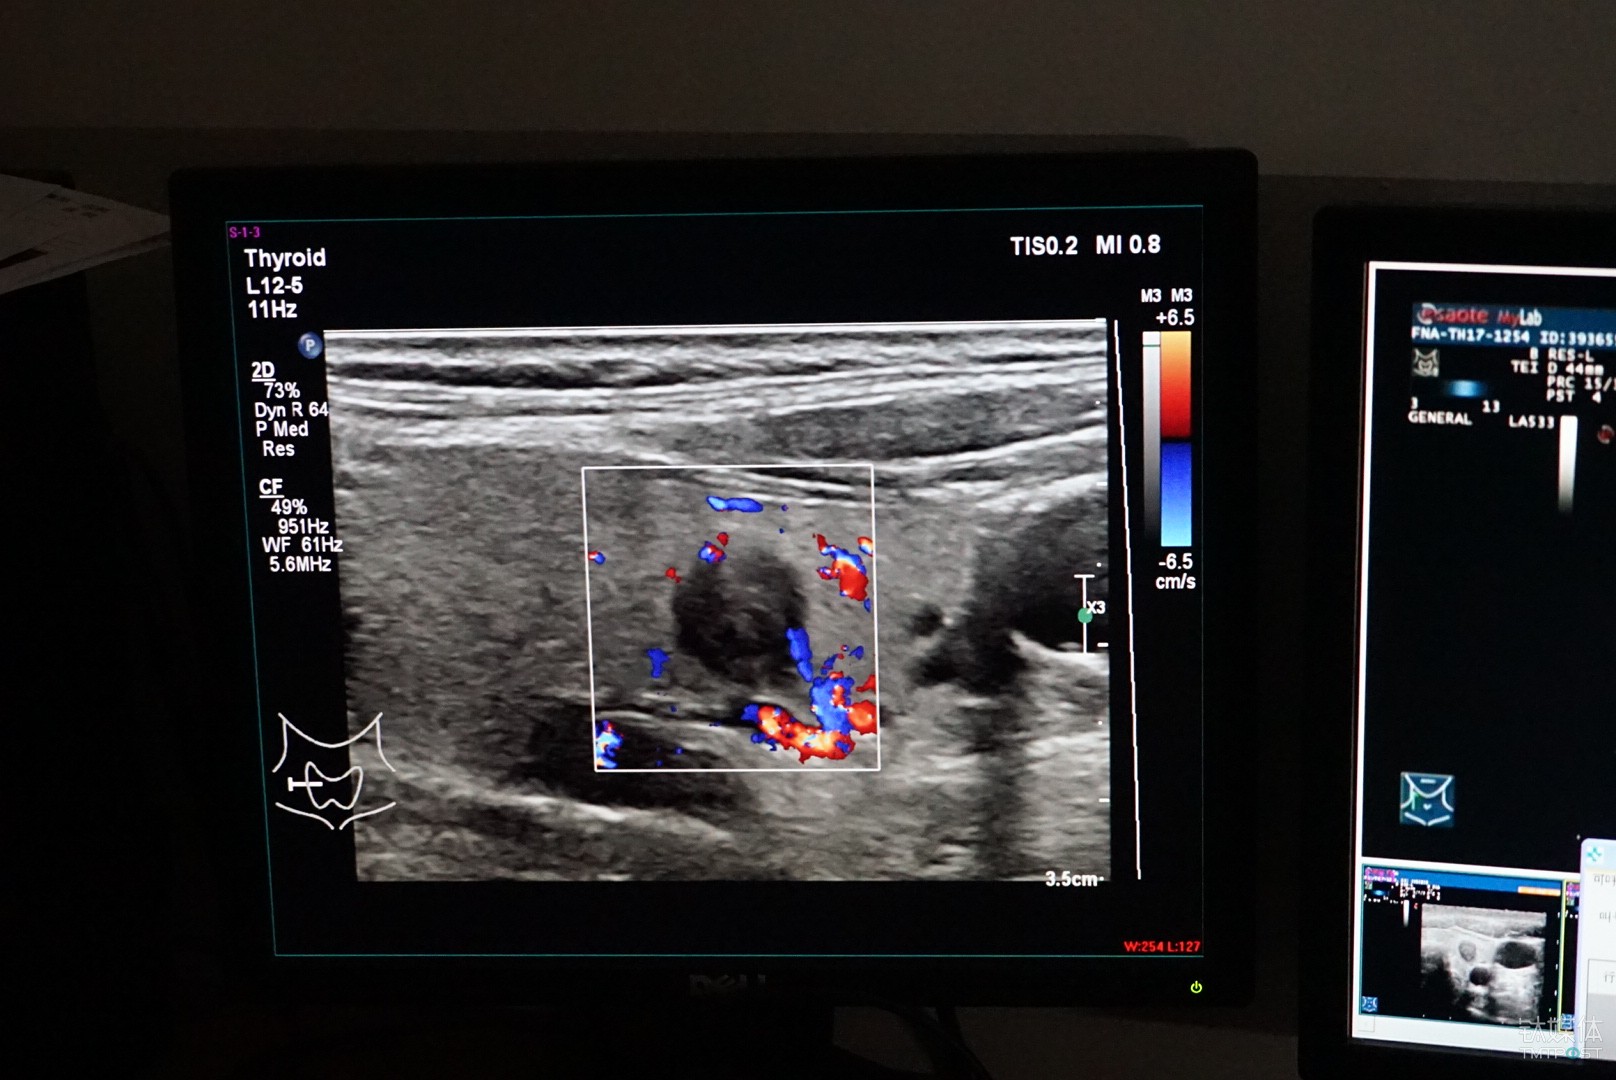

類似的案例也出現(xiàn)在了浙江大學(xué)附屬第一學(xué)院的超聲醫(yī)學(xué)科,該病院是率先嘗試用人工智能方式輔助診斷甲狀腺結(jié)節(jié)的醫(yī)學(xué)機構(gòu)。

具體而言,這是一套由德尚韻興與浙江大學(xué)特聘教授孔德興團(tuán)隊主導(dǎo),依托英特爾至強融合處理器平臺開發(fā)而來的輔助診斷系統(tǒng)。

從功能上來說,這是一套基于超聲波影象的甲狀腺結(jié)節(jié)良惡性的輔助診斷系統(tǒng),按照甲狀腺結(jié)節(jié)檢查時候拍攝的醫(yī)學(xué)影像的特征,通過對圖像的識別和標(biāo)注,來幫手醫(yī)生更準(zhǔn)確的做出診斷結(jié)論。

對于甲狀腺結(jié)節(jié)的檢查目前主要依靠超聲的方式,相較于CT和核磁,超聲的好處是自制、靈活、無副作用,所以它也是目前臨床醫(yī)學(xué)使用最為廣泛的一種檢測手段,不足之處是圖像不清楚、造影比較大,它對醫(yī)生的要求就比較高。

浙江大學(xué)第一附屬病院超聲科趙主任向鈦媒體體現(xiàn),起初對這種系統(tǒng)也是半信半疑,因為涉及到病人診斷結(jié)果,如果不靠譜的話產(chǎn)生的危害非常大,但是嘗試幾次之后發(fā)現(xiàn),確實能提升醫(yī)生的工作效率。

計算機視覺對圖像的處理,傳統(tǒng)的機器學(xué)習(xí)是報答定義特征,由于目前收集到的數(shù)據(jù)來源于多家病院,尺度和規(guī)范不統(tǒng)一,德尚韻興專門采用了一種有監(jiān)督的深度學(xué)習(xí),讓醫(yī)生對數(shù)據(jù)進(jìn)行標(biāo)注,每一個培訓(xùn)的樣本都是醫(yī)生人工標(biāo)注的,結(jié)節(jié)的大小、位置,還包孕病人的其他的病理特征,之后再反饋給機器進(jìn)行訓(xùn)練。

按照德尚韻興總經(jīng)理胡海蓉提供的,“目前三甲病院醫(yī)生的平均準(zhǔn)確率為60%-70%,基層病院會更加低一些,而輔助診斷系統(tǒng)目前準(zhǔn)確率可以達(dá)到85%以上,不過由于在我國人工智能還沒有行醫(yī)資格,所以我們將其定位為輔助診療,只是給醫(yī)生提供一些參考?!?/p>